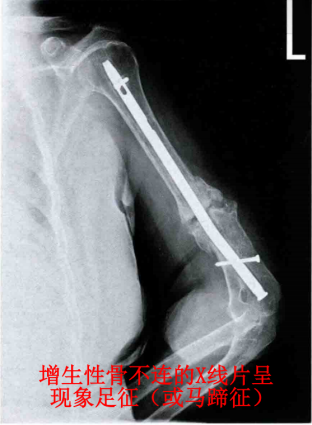

②马蹄形骨不连

骨折端中度增生,形成少量的骨痂,稳定情况比较差,新骨形成比较不明显。

多由于钢板螺钉内固定后中等程度不稳定,骨折断端形成一定的骨痂但不足以愈合,并且可能存在少量的硬化。

1、增生性(肥大性)骨不连

骨折端的生物学环境良好,有良好的血供和生物活性。

骨折端缺乏足够稳定的生物力学环境,骨折端活动过度,产生大量的软骨性骨痂。

X 线片呈现出「象足征」或「马蹄征」。